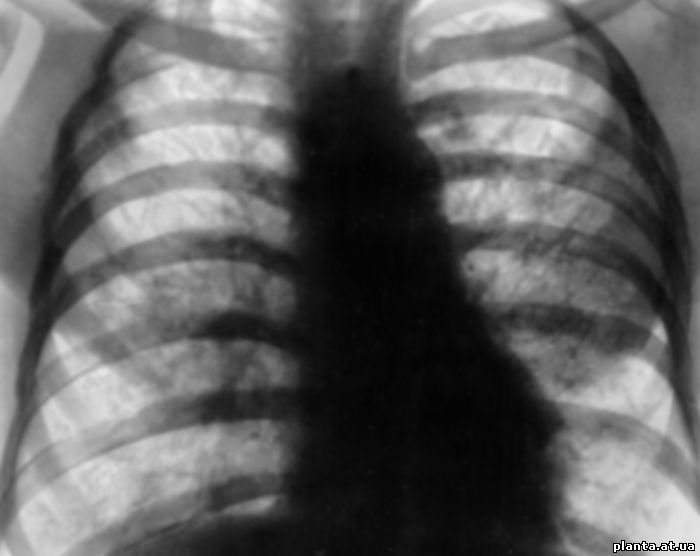

При объективном исследовании определяется укорочение перкуторного тона, преимущественно в нижних отделах легких. При аускультации - ослабленное везикулярное дыхание, реже - нежные крепитирующие хрипы. Клинический и биохимический анализы не содержат каких-либо признаков, характерных для альвеолярного протеиноза легких. У некоторых больных в крови определяется повышение уровня холестерина, кальция. При рентгенологическом исследовании легких выявляются мелкоочаговые тени, сливающиеся друг с другом, с преимущественно базальной и прикорневой локализацией. Эти изменения, как правило, двусторонние. Бронхоскопия малоинформативна. Диффузионная способность легких снижается, медленно прогрессируют рестриктивные нарушения вентиляции, при физической нагрузке выявляется гипоксемия.